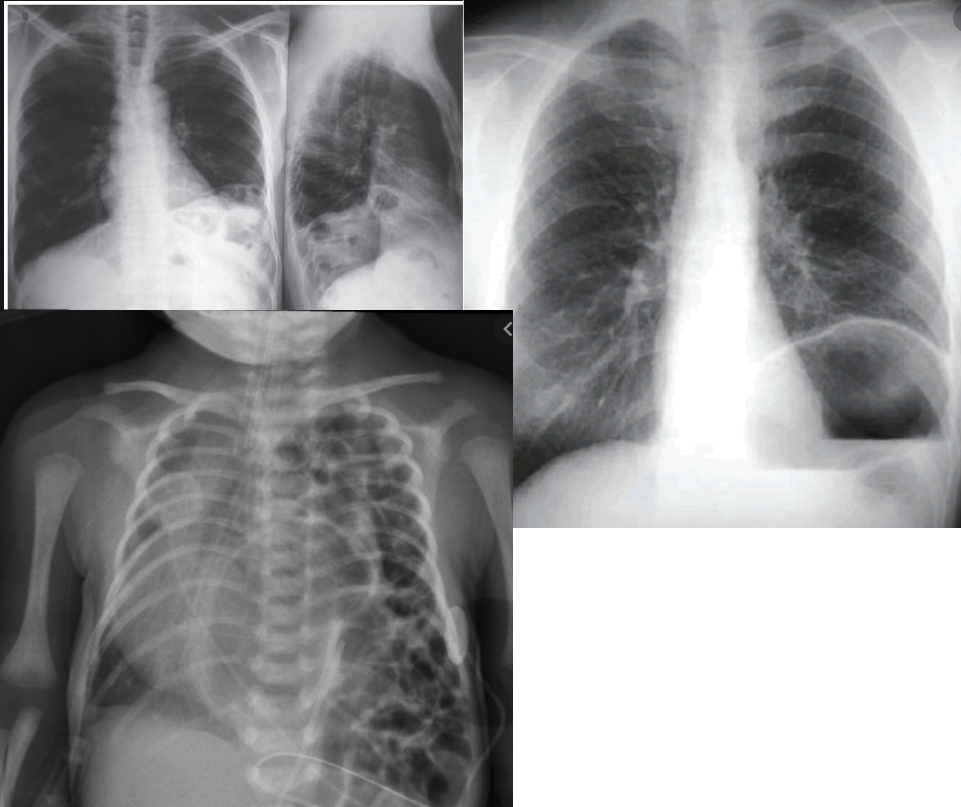

Imagem regiões anatômicas do abdome e transição toracoabdominal (TTA).

Limite superior anterior: linha horizontal ao nível dos mamilos. Limite inferior anterior: gradio costal. Limite superior posterior: ângulos inferiores das escápulas.